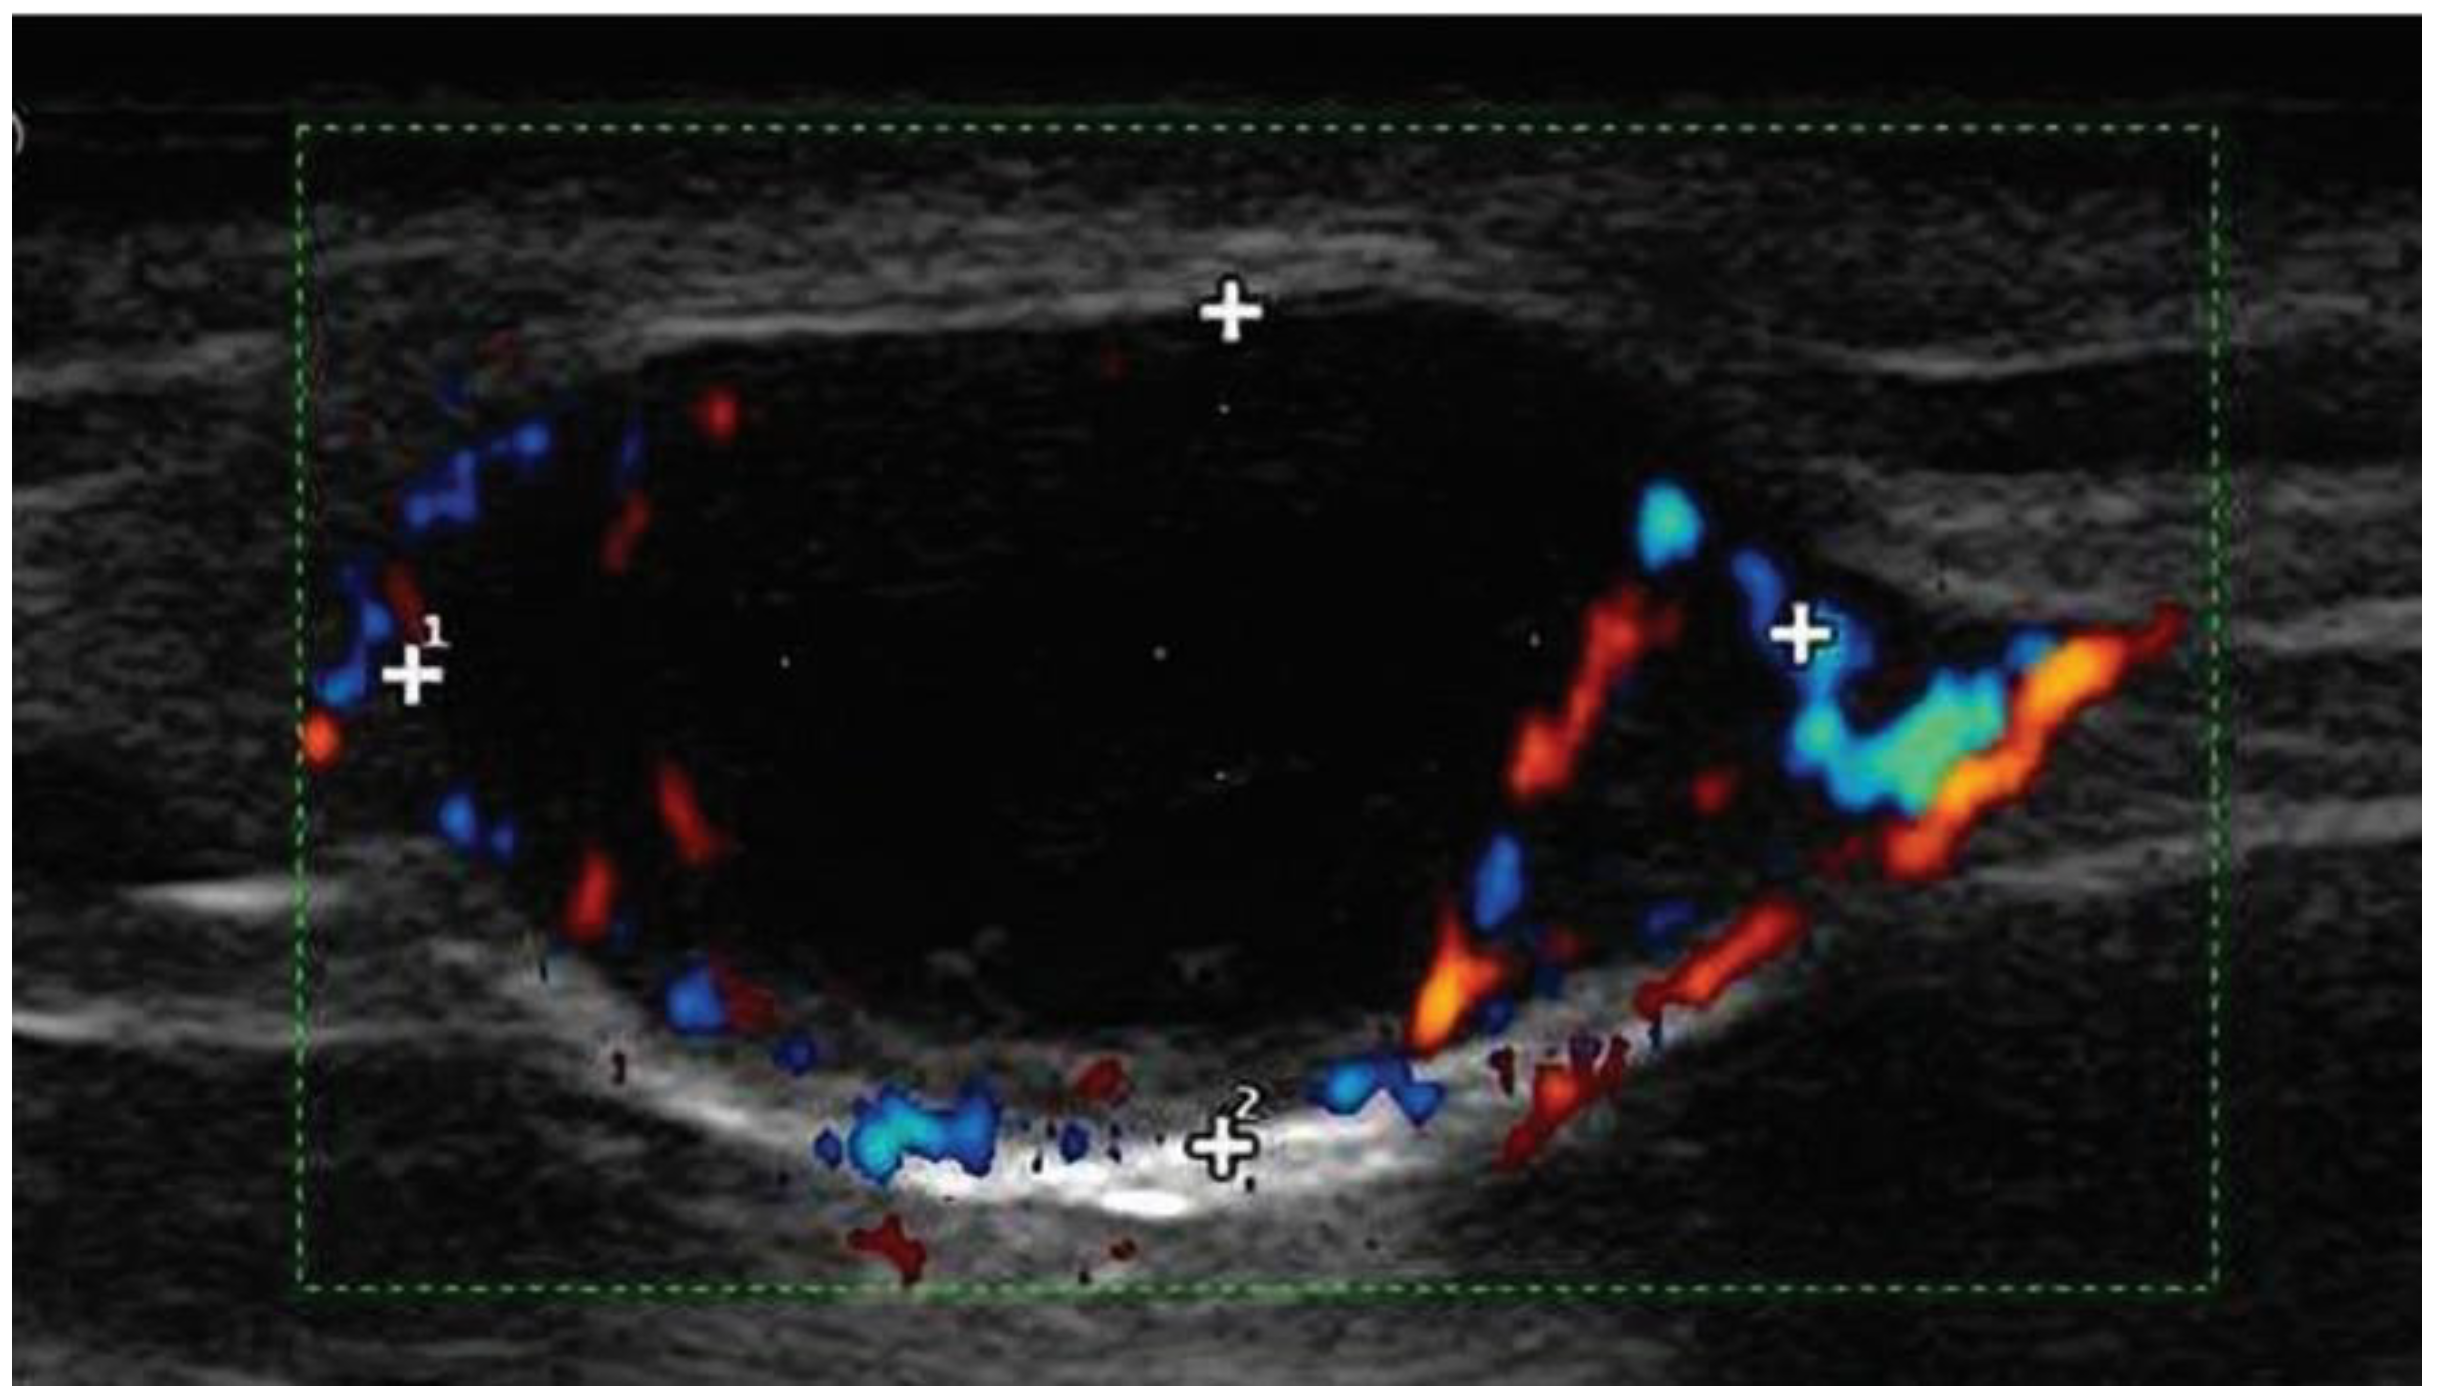

11.1. Ultrasounds of Nodal Basins

- Ulrich, J.; van Akkooi, A.C.; Eggermont, A.M.; Voit, C.A. Sonographic criteria for diagnosing sentinel node metastases in melanoma patients. Ultraschall Med. 2015, 36, 149–153. [Google Scholar] [CrossRef] [PubMed]

- Voit, C.; Van Akkooi, A.C.; Schafer-Hesterberg, G.; Schoengen, A.; Kowalczyk, K.; Roewert, J.C.; Sterry, W.; Eggermont, A.M. Ultrasound morphology criteria predict metastatic disease of the sentinel nodes in patients with melanoma. J. Clin. Oncol. 2010, 28, 847–852. [Google Scholar] [CrossRef]